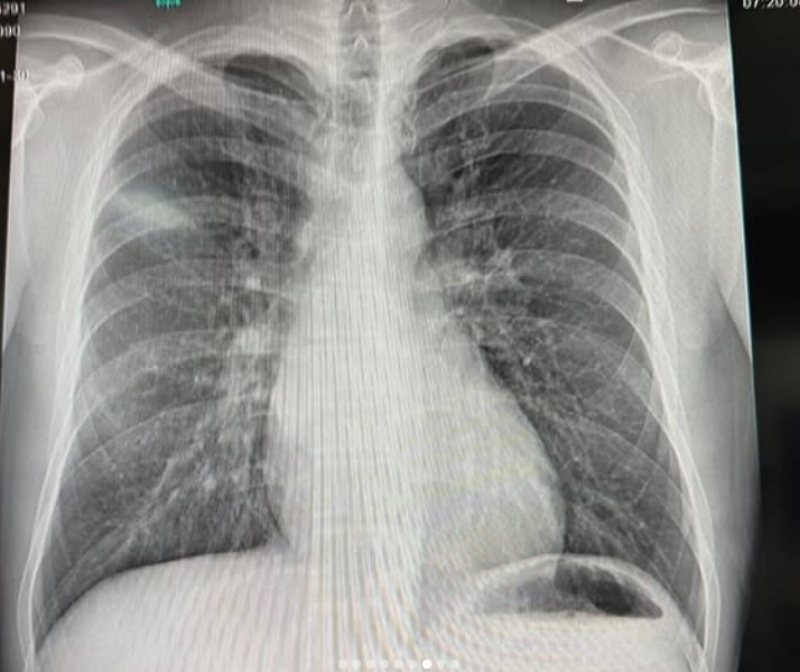

เรียกได้ว่า เป็นนักร้องหนุ่มชื่อดัง อย่าง โต้ง ทูพี ที่ล่าสุดทำเอาแฟนๆต่างเป็นห่วงหนักมาก เมื่อจ้าตัวโพสต์อินสตราแกรม @twopee เผยคลิปวินาทีเล่นสกีหิมะ พร้อมภาพเอ็กซเรย์ ตรวจพบซี่โครงหัก โดยระบุแคปชั่นบอกว่า "จะออกไปแตะขอบฟ้า, ซี่โครงหัก 1 ท่อน Phuket see yall tonight!!